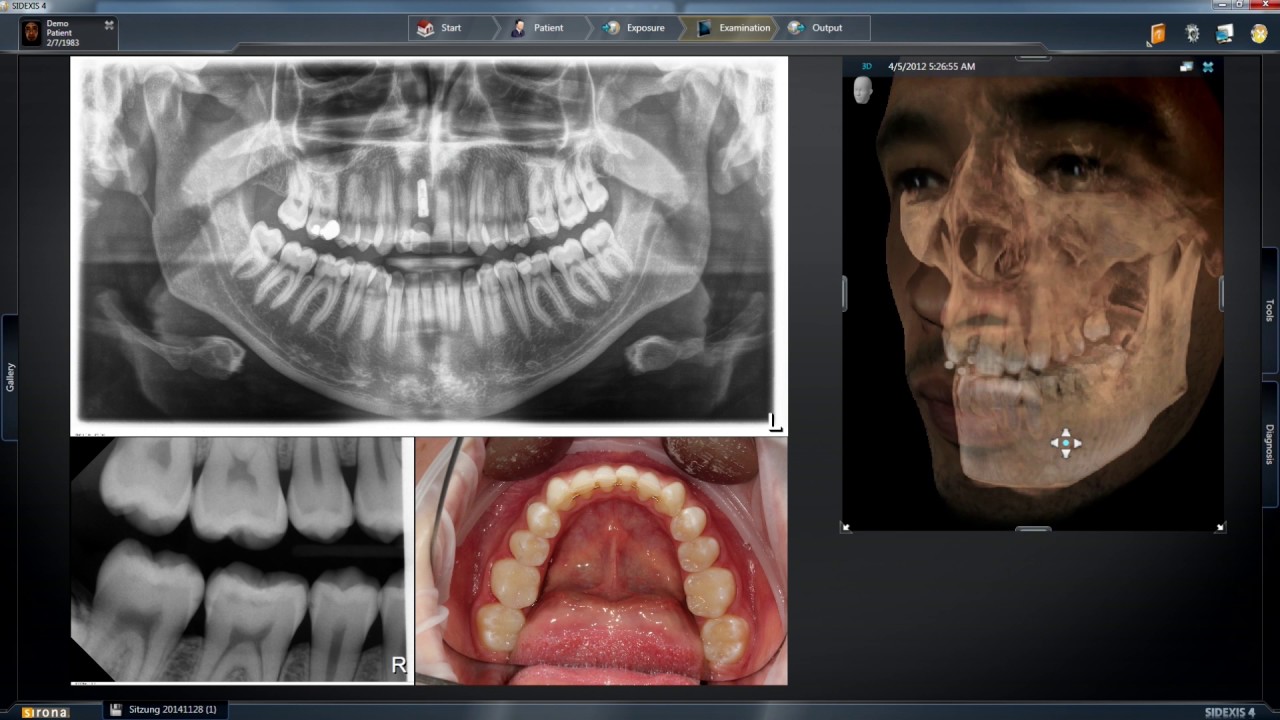

At Ashburn Dental Care our Dental Implants service, which has been in development since 1996 aims to Increase the success rate of dental implants by using cutting edge Galileos 3D software technology to plan (Hiossen) implants for our patients. The final screw-retained crown returns our patient to having a beautiful smile restoring confidence, and are fixed into place unlike dentures.

At Ashburn Dental Care we begin your individualized plan with a 3D x-ray of the patients jaw to plan the location and viability of the implants. They will also ensure that the grafted bone has time to heal by leaving three months between the tooth extraction/grafting and the crown installment. Ashburn Dental Care chose to make this move because allowing for time between the tooth extraction/grafting and installing the screw-retained crown ensures that the bone graft is fully healed and ensures a better bond between the implant and the bone.